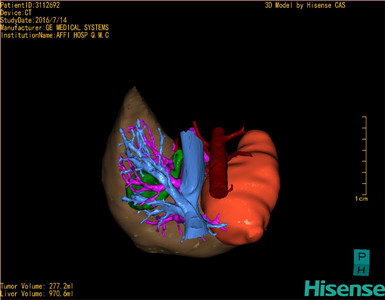

将0.625mm双源薄层CT资料的静脉期和动脉期Dicom格式文件导入海信CAS系统。

通过调节窗宽窗位调整CT序号,对肿瘤,肝实质,胆囊,下腔静脉,肿瘤,肝动脉、门静脉及肝静脉等进行三维重建;系统自动计算肿瘤体积和肝脏体积。

模拟手术操作,自动计算切除肿瘤体积。肝脏体积为970.6ml,肿瘤体积为277.2ml,肿瘤体积为肝脏体积的28.6%,通过比对60-70岁正常肝脏体积为1262.7±284.31 ml,通过术前模拟手术,精准判断切除后剩余肝脏体积能耐受,避免肝衰竭发生。

术前手术方案的规划。

术前三维重建:

重建图片